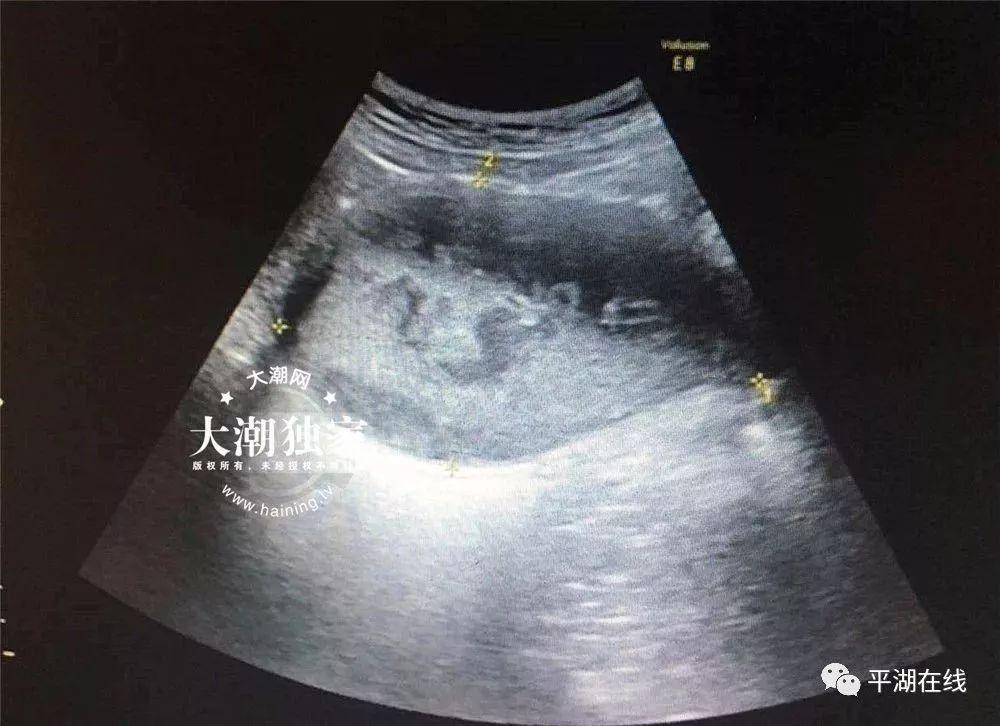

接诊的医生询问了小燕的病情后,当场就觉得小燕的情况有些特别,于是马上给小燕安排了B超和妇科检查。

△小燕的B超报告

根据检查,医院妇科主任俞丽娟判断,小燕得了处女膜闭锁伴盆腔感染!需要马上住院进行手术治疗。